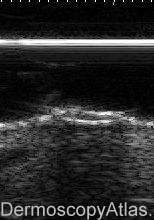

Description: Lateral view to match sagital HFUS section

Note double hyperechoic line which is chitinous exoskeleton of the parasite